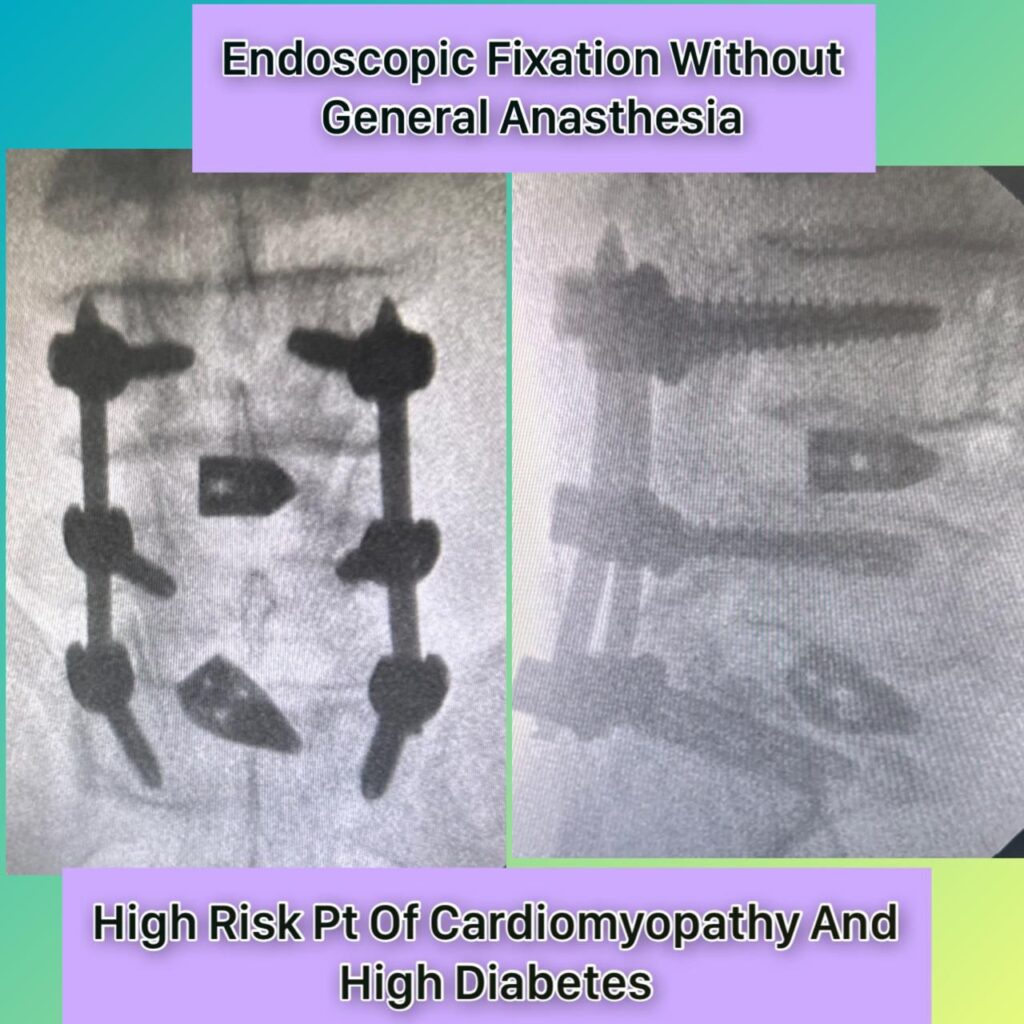

Dr. Ridham Khanderia, MBBS, MS (General Surgery), MCh (Neurosurgery) is a Neuro and Spine Surgeon with over 4 years of clinical experience and more than 2,000 neurosurgical and spine procedures performed. He completed his MBBS from PDU Medical College, MS in General Surgery from MP Shah Medical College, and MCh in Neurosurgery from AIIMS Rishikesh. He also holds a Fellowship in Endoscopic Spine Surgery from Pune.

He specializes in back pain, slip disc, sciatica, and complex spine and brain disorders, with a strong focus on conservative treatment, minimally invasive surgery, and ethical, patient-centered care.